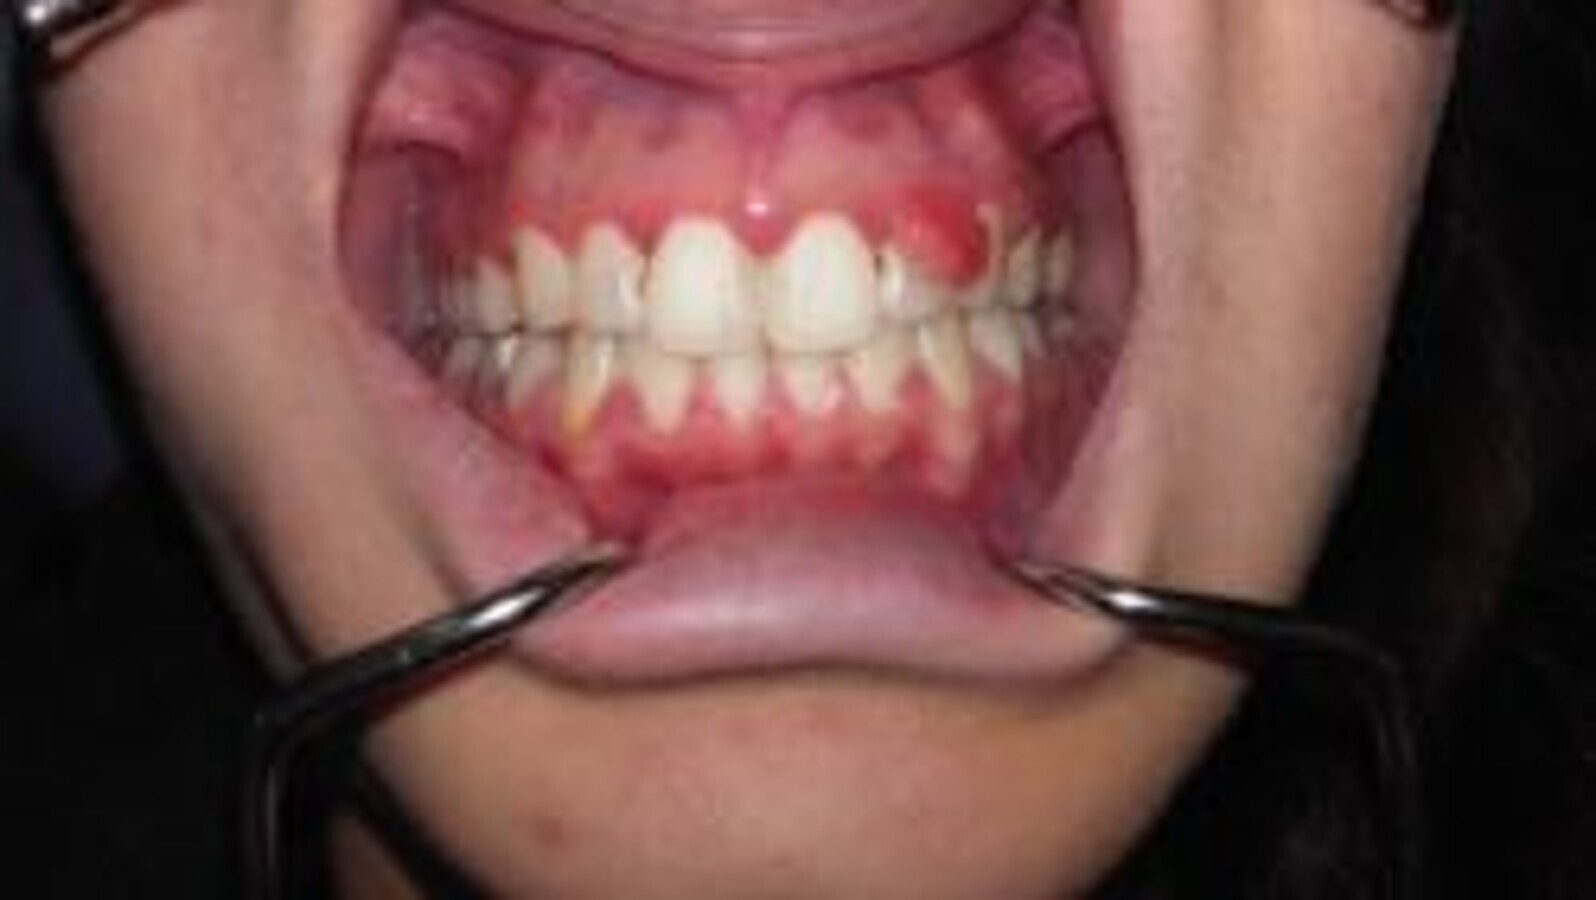

Lorsque la gingivite n’est pas traitée, le processus inflammatoire peut se développer en profondeur et

provoquer la destruction du système d’attache des dents avec apparition de poches parodontales et

perte osseuse objectivable sur la radiographie [Fig 2 ,3]

Fig. 2 : Parodontite chez une femme enceinte de 7 mois, noter l’inflammation gingivale, l’augmentation de volume gingival, formation de poches parodontales et perte d’attache.